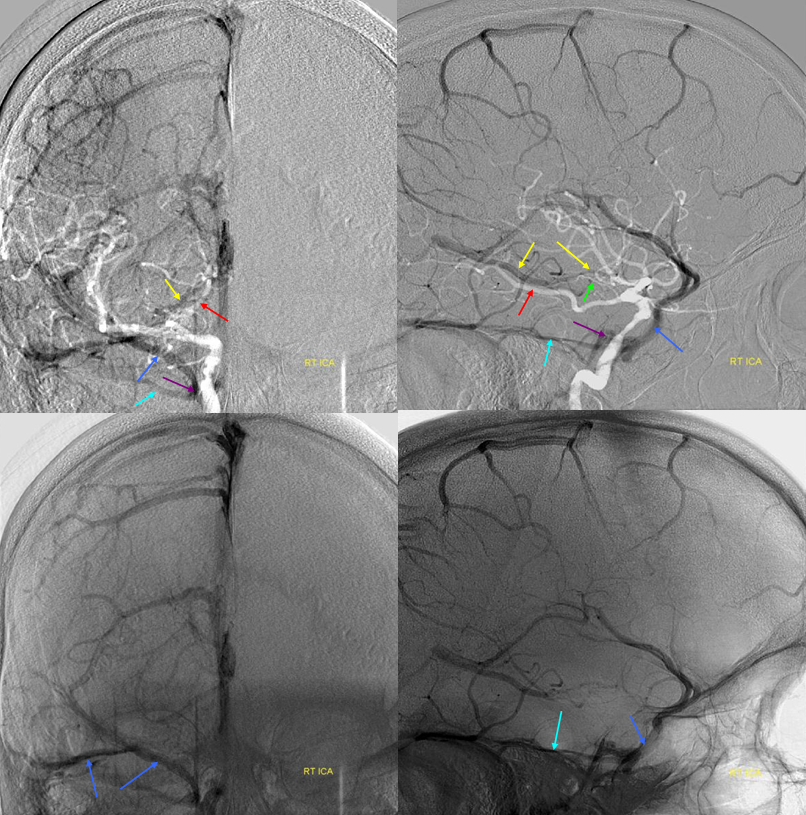

Below is a case of severe venous sinus thrombosis and secondary parenchymal venous infarcts

The explanation for the above tragic pattern is below. On the right, sigmoid and transverse sinuses are patent. However, the Labbe is hypoplastic, and majority of outflow used to go to the Trolard, into the now occluded SSS. There is no other effective way to go — the trolard tries to decompress via a left diploic vein, and convexity tries to access the deep venous system (which normally should not be well-seen in setting of hypoplastic right A1 segment). The left situation is much better, as well-developed superficial sylvian veins drain into the patent Cavernous Sinus. Thus, despite thrombosis of the left transverse and sigmoid sinuses, the left hemisphere is doing better, while the right one, which has patent transverse and sigmoid sinuses, is devastated.

Post venous thrombectomy — with limited results. Note presence of same left diploic vein as seen in right ICA injection, and connection between the distal superior sagittal sinus and the deep venous system via the inferior sagittal sinus.